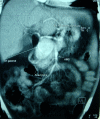

Gastroduodenal artery aneurysm is a rare vascular lesion, asymptomatic in the majority of cases. However, ruptured aneurysm is associated with poor prognosis and mortality can achieve a 40% rate. We here report the case of an 83-year-old patient with abrupt onset of non-specific abdominal pain associated with hematemesis. Endoscopy showed beating formation compressing the duodenal bulb with active bleeding. Abdominal computed tomography (CT) scan was performed which objectified gastro duodenal artery aneurysms involving the artery ostium and making endovascular treatment impossible to perform. Thus, the patient underwent open surgery based on flattening associated with aneurysm exclusion and then complemented by bulb plasty. Post-operative CT scan confirmed total exclusion of the aneurysm with preservation of hepatic circulation.